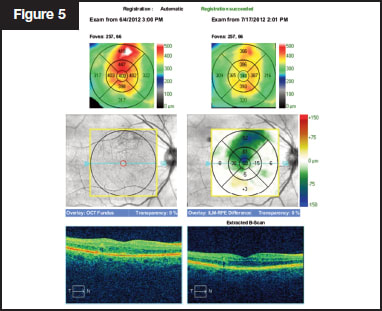

This 61-year-old man presented with center-involving diabetic |